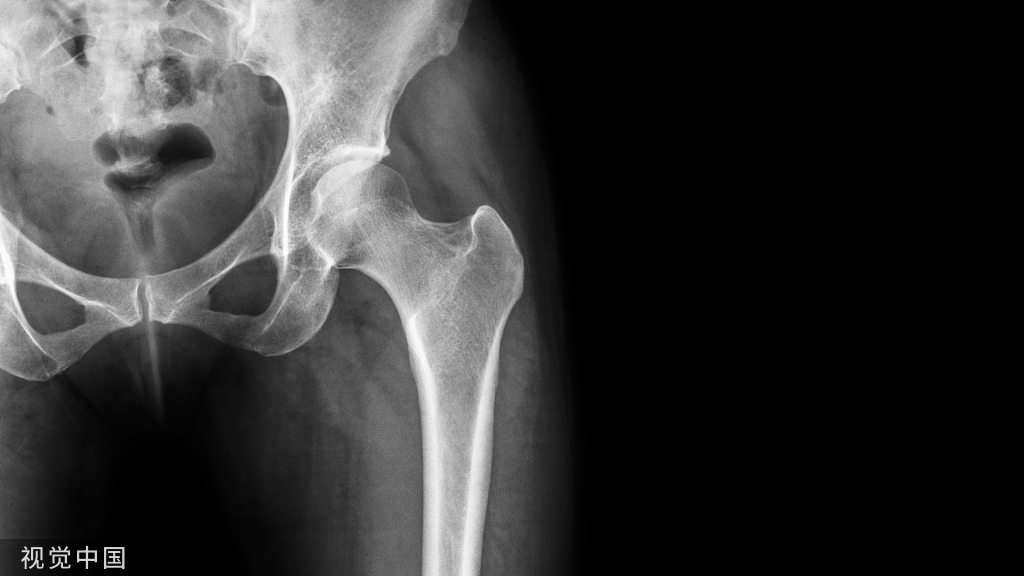

临床表现:股骨颈疝窝是发生于股骨头基底和股骨颈近端的一种较为少见的良性病变,发病率约 4%~5%,好发于中老年人,临床多无明显症状,常因其他病变检查时偶然发现。多位于股骨头基底和股骨颈前外侧 皮质下,可呈圆形或卵圆形。

影像表现:X 线平片上表现为伴有清晰薄层硬化缘的环形(囊状)透亮区,CT 上表现为圆形 或类圆形的皮质下局灶性骨质缺损,周围见薄层硬化带环绕,边缘锐利,部分较大病灶在病灶层面或上下相邻、层面上前方显示皮质与病灶相通的局部裂隙样缺损病灶,最大径线通常小于 10 mm;MRI 示病灶在 T1WI 上呈低信号,在 T2WI 上呈均匀或不均匀高信号。